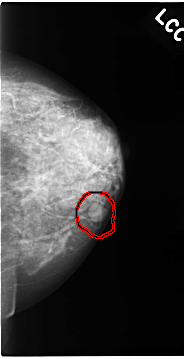

C_0064_1.LEFT_CC

FILE: C_0064_1.LEFT_CC.OVERLAY

TOTAL_ABNORMALITIES 1

ABNORMALITY 1

LESION_TYPE MASS SHAPE OVAL MARGINS CIRCUMSCRIBED

ASSESSMENT 3

SUBTLETY 5

PATHOLOGY BENIGN

TOTAL_OUTLINES 1

BOUNDARY